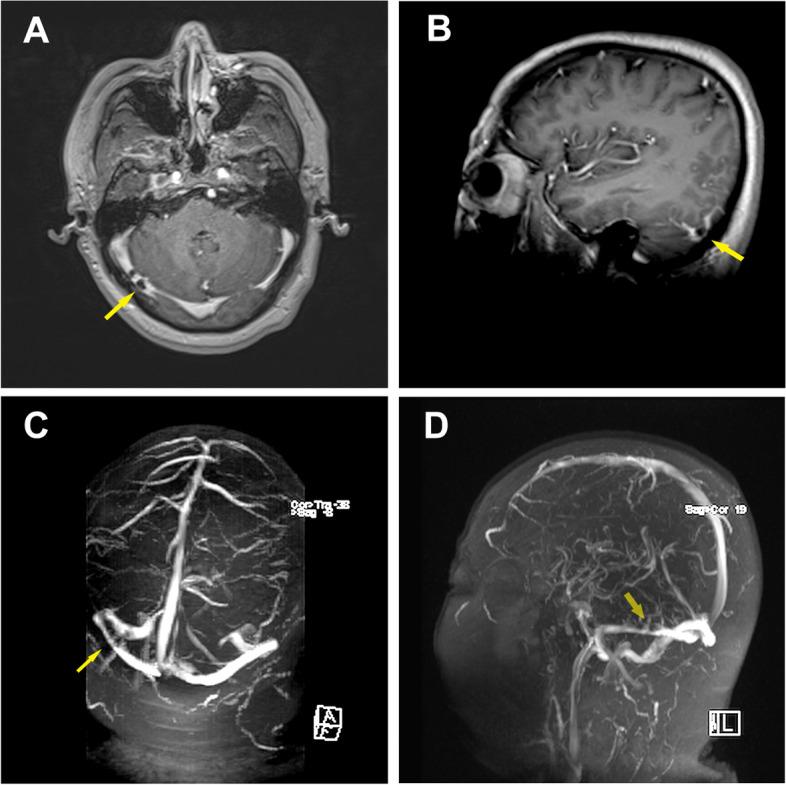

A 54-year-old male patient came to our department with a fever for 2 days and altered mental status for 1 day. Abdominal computed tomography (CT) and liver magnetic resonance imaging (MRI) revealed multiple liver abscesses. The blood culture was identified as Klebsiella pneumoniae sepsis. Head contrast-enhanced MRI and magnetic resonance venography (MRV) imaging showed multiple thrombus formation in the right transverse sinus and sigmoid sinus. The patient's infection and thrombosis were controlled within one week of multidisciplinary comprehensive treatment such as antibiotic and antithrombotic therapy, and a good clinical recovery during the 1-month follow-up.

一名 54 岁男性患者因发热 2 天伴精神状态改变 1 天来我院就诊。腹部 CT 和肝脏 MRI 显示多发肝脓肿。血培养鉴定为肺炎克雷伯菌败血症。头部增强 MRI 和磁共振静脉造影(MRV)成像显示右侧横窦和乙状窦多发血栓形成。经过多学科综合治疗(如抗生素和抗血栓治疗)一周后,患者的感染和血栓得到控制,在 1 个月的随访期间临床恢复良好。